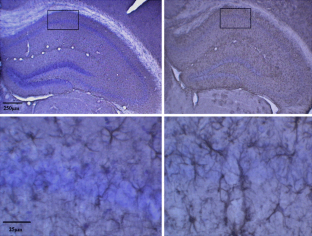

Fig. 1